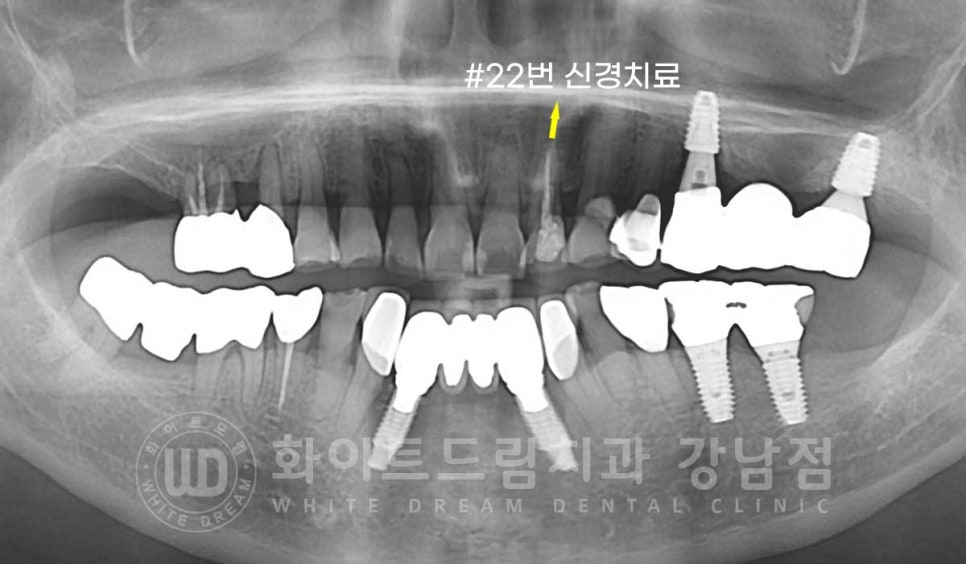

환자분은 어떤 치아를 치료하기로 했을까요?

환자분은 입이 굉장히 크신 분이셔서 웃거나 말할 때 노출되는 치아가 많았습니다.

그래서 마모도가 심한 앞니 6전치를 개선하기로 결정했고

이 중 신경치료가 되어있는 22번 치아는 라미네이트 치료보다는 크라운으로 360도 감싸서

치아를 보호해 주는 것이 좋기에

13, 12, 11, 21, 23번 치아는 라미네이트 치료를

22번 치아는 올 세라믹 크라운으로

치료를 진행하기로 결정했습니다.